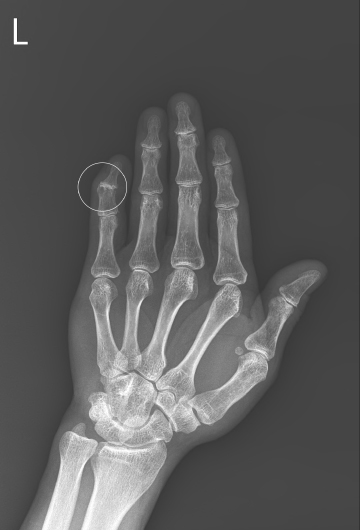

수술전

2021.10.30

수술후

2022.03.25